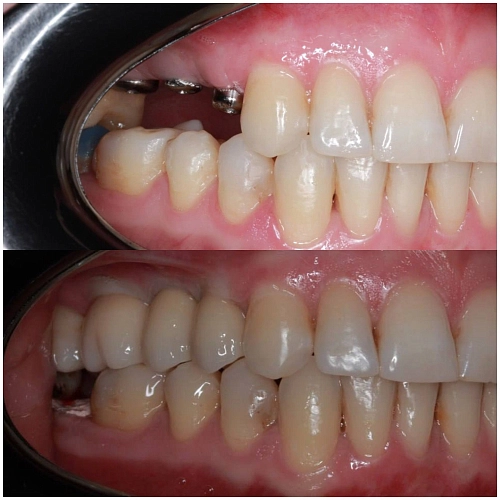

На фото работа врача-ортопеда Андреева ДП